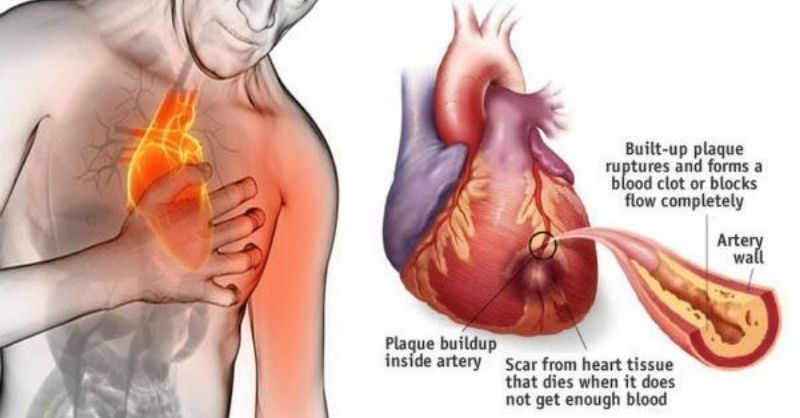

How to Prevent a Heart Attack with Cayenne Pepper

Did you know that a common ingredient in your kitchen might be able to save someone from a heart attack in just 60 seconds? Herbalist John Christopher, though...